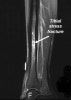

MRI로도 확진이 가능하지만 가음성으로 나올 수도 있습니다.

영상의학적 소견은 반드시 '통증과 압통이 있는 부위 검진'의 임상소견과 같이 고려해야 합니다.

MRI : Tibial stress fracture